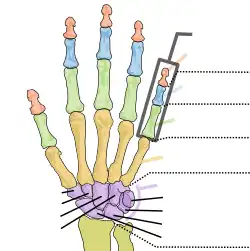

Carpal bones

Labelled image showing the eight carpal bones. | |

The carpal bones are the eight small bones that make up the wrist (carpus) that connects the hand to the forearm. The terms "carpus" and "carpal" are derived from the Latin carpus and the Greek καρπός (karpós), meaning "wrist". In human anatomy, the main role of the carpal bones is to articulate with the radial and ulnar heads to form a highly mobile condyloid joint (i.e. wrist joint),[1] to provide attachments for thenar and hypothenar muscles, and to form part of the rigid carpal tunnel which allows the median nerve and tendons of the anterior forearm muscles to be transmitted to the hand and fingers.

The eight carpal bones may be conceptually organized as either two transverse rows, or three longitudinal columns.

When considered as paired rows, each row forms an arch which is convex proximally and concave distally. On the palmar side, the carpus is concave and forms the carpal tunnel, which is covered by the flexor retinaculum.[2] The proximal row comprises the scaphoid, lunate, triquetral, and pisiform bones which articulate with the surfaces of the radius and distal carpal row, and thus constantly adapts to these mobile surfaces. Within the proximal row, each carpal bone has slight independent mobility. For example, the scaphoid contributes to midcarpal stability by articulating distally with the trapezium and the trapezoid. In contrast, the distal row is more rigid as its transverse arch moves with the metacarpals.[3]